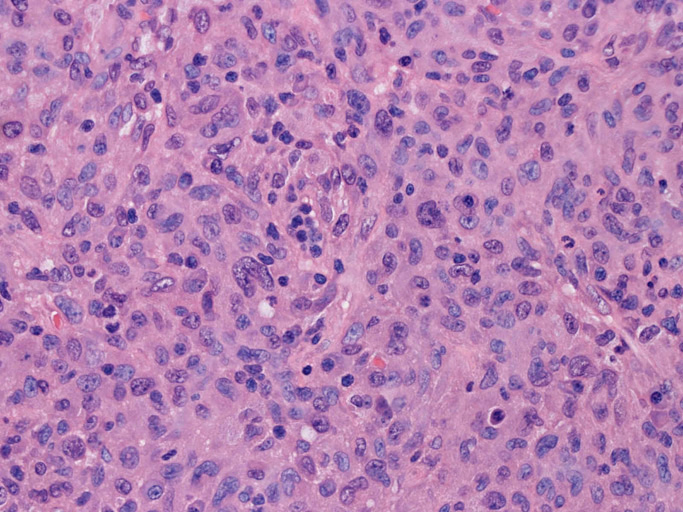

大型細胞の増殖よりなる腫瘍。縦溝,しわ,切れ込みのある核をもった大型細胞も出現する。クロマチンは顆粒状で核小体も明瞭である。核分裂は >50/10hpfと多い。eosinophilsは少ない。壊死が多発することがある。未分化ないし低分化な細胞像, 組織所見のため鑑別診断は多岐にわたり、的確な免疫染色を行う必要がある。

皮膚に異型細胞の浸潤がみられる。異型細胞は表皮内に浸潤するほか、表皮真皮境界部, 真皮, 皮下脂肪組織にもびまん, 結節様の浸潤所見を示す。血管周囲に浸潤、集蔟する所見も多く見られる。 増殖浸潤細胞の核には類円形や腎臓形, またはへこみ, 切れ込み, 溝などを有する多型な核が認められる。クロマチンは粗でvesicularな核が多い。核小体の明らかな核もある。好エオジン性の核内封入体様構造も少数に見られた。mitosisは容易に認められる。hyperchromaticな多型核, bizzarreな細胞が高頻度に認められ異型度は高いと考えられる。細胞質は境界不明瞭, 淡明または泡沫様の 好エオジン性胞体である。

免疫染色 浸潤細胞はCD1a+, S100+, Langerin+, HLA-DR+, CD4+, CD45+, CD68+. MIB-1 index:24.4%